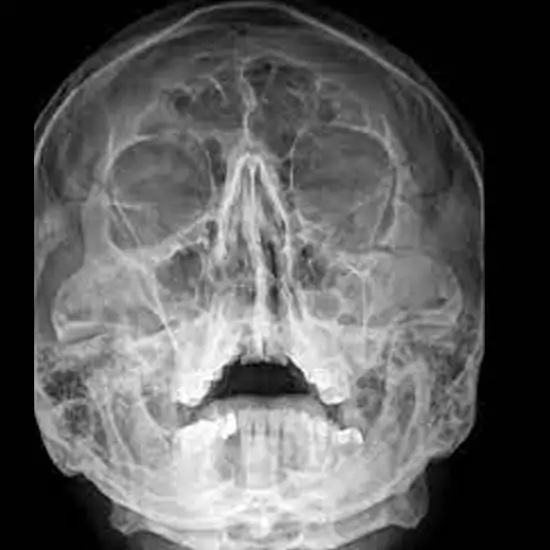

The cheekbone length can be seen on an X-ray of the zygomatic arch test. The two zygomatic bones, the temporal bone, and the skin and muscles around them make up the zygomatic arch.

• To identify anomalies, malformations, uneven development, or broken/fractured cheekbones.

• Detecting zygomatic arch before delivery when the infant cannot open its mouth (congenital mandibular-zygomatic arch synostosis).

• To locate a zygomatic arch tumor.